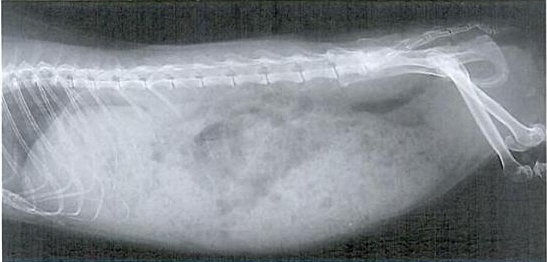

Ukoliko se plinovi ne riješe unutar par dana, potrebno je pronaći točan uzrok, pri čemu može pomoći RTG snimak.

Snimka plinovima ispunjenog abdomena: